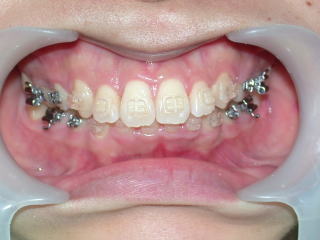

2023年9月11日

2024年2月20日

2024年5月15日装置除去